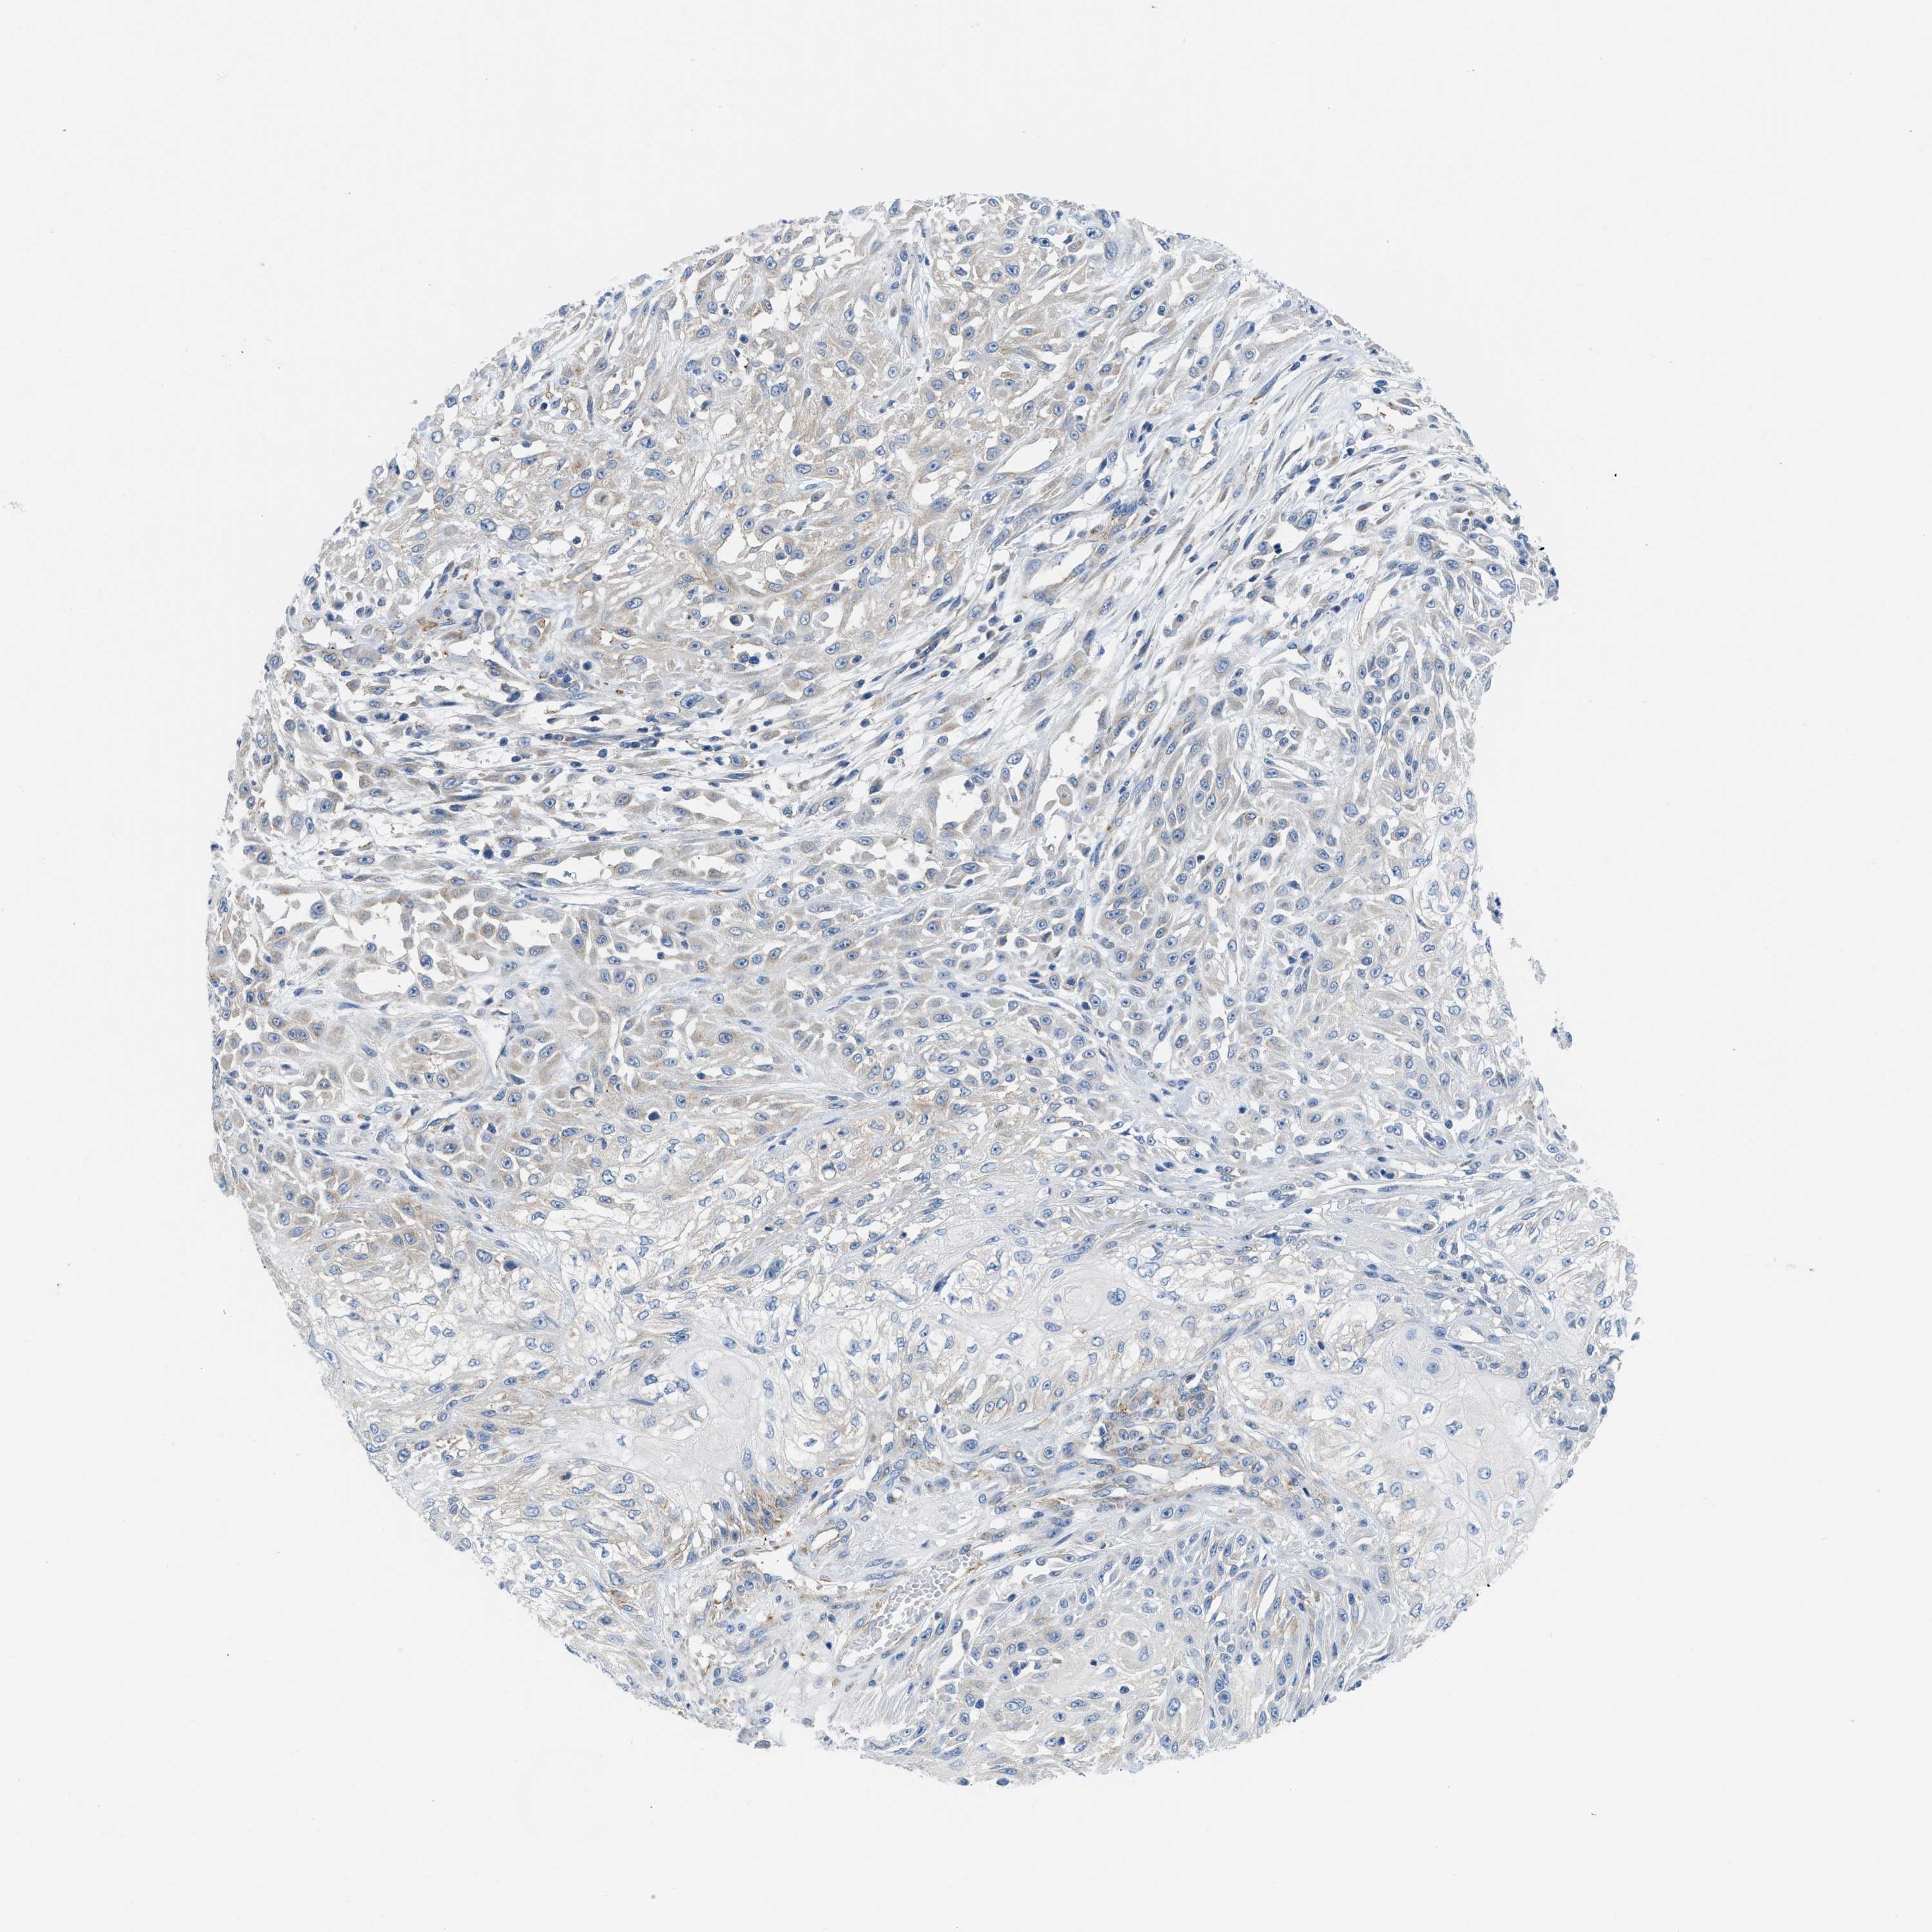

SKIN CANCER - Protein expressioni

A mouse-over function shows sample information and annotation data. Click on an image to view it in a full screen mode. Samples can be filtered based on level of antibody staining by selecting one or several of the following categories: high, medium, low and not detected. The assay and annotation is described here.

Antibody stainingi

Antibody staining in the annotated cell types in the current human tissue is reported as not detected, low, medium, or high, based on conventional immunohistochemistry profiling in selected tissues. This score is based on the combination of the staining intensity and fraction of stained cells.

Each image is clickable and will lead to virtual microscopy that enables deeper exploration of all samples and also displays staining intensity scores, fraction scores and subcellular localization as well as patient and tissue information for each sample.

Antibody HPA018525

Staining

High

Medium

Low

Not detected

Intensity

Strong

Moderate

Weak

Negative

Quantity

>75%

75%-25%

<25%

None

Location

Nuclear

Cytoplasmic/membranous

Cytoplasmic/membranous,nuclear

Squamous cell carcinoma, NOS